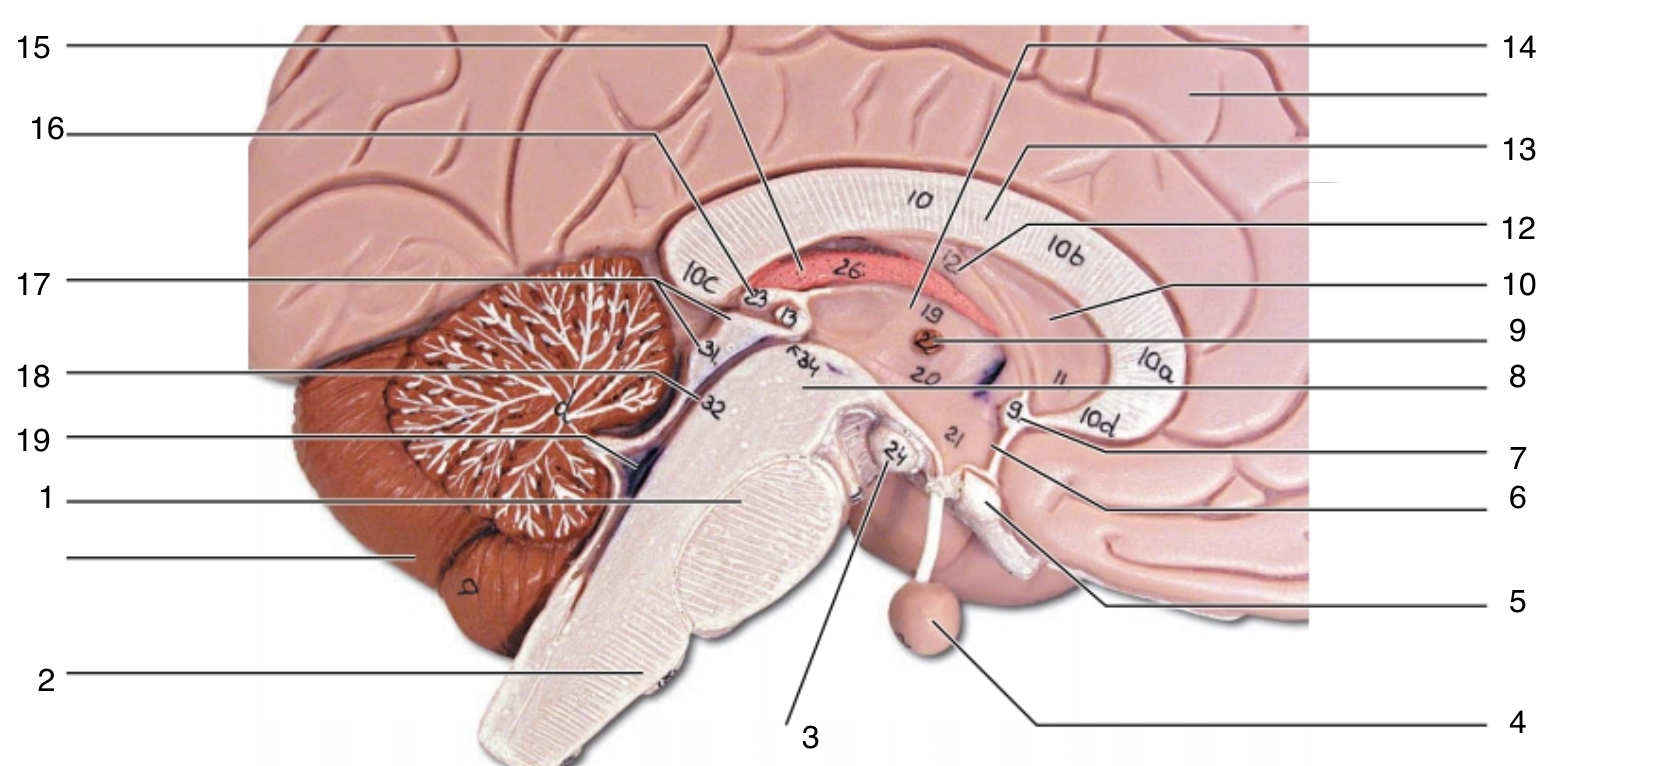

Brain Stem

1

pons

1

2

medulla oblongata

2

3

mammillary body

3

4

pituitary gland

4

5

optic chiasma

5

6

hypothalamus

6

7

anterior commissure

7

8

midbrain

8

9

interthalamic adhesion

9

10

septum pellucidum

10